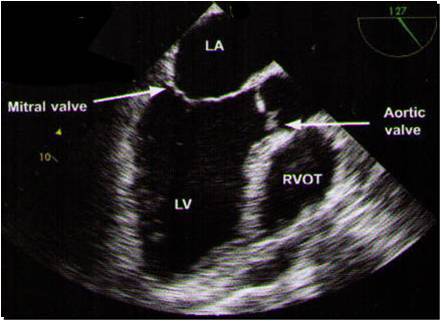

This is looking down to aortic valve

I think this might be the most important picture for TEE

a long axis view